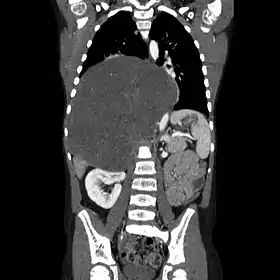

![]() صورة بالأشعة المقطعية لورم عصبي عقدي كبير الحجم في التجويف الصدري. صورة بالأشعة المقطعية لورم عصبي عقدي كبير الحجم في التجويف الصدري. | |